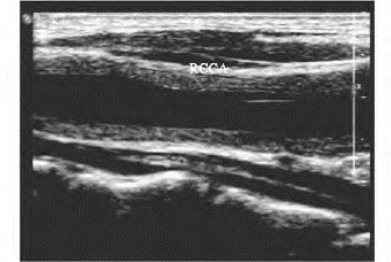

1.26.3三、正常血管

1.26.4四、动脉闭塞性疾病